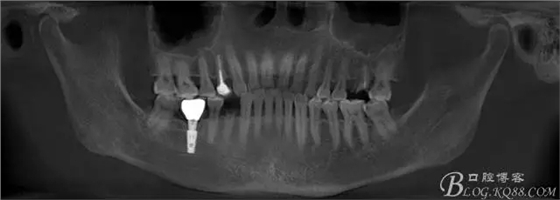

那么看下術(shù)前CBCT吧

上圖為術(shù)前CBCT情況,26號(hào)牙顯示頰根和腭根間有一比較大的區(qū)域骨頭吸收,對(duì)于即刻種植還是有難度的,植入深度需要適當(dāng)加深,那么也許使用BICON 種植體相對(duì)更加合適

上圖44號(hào)牙位做即刻種植毫無難度可言,我們要做的只是患者術(shù)后反應(yīng)更小,植入方向更好而已